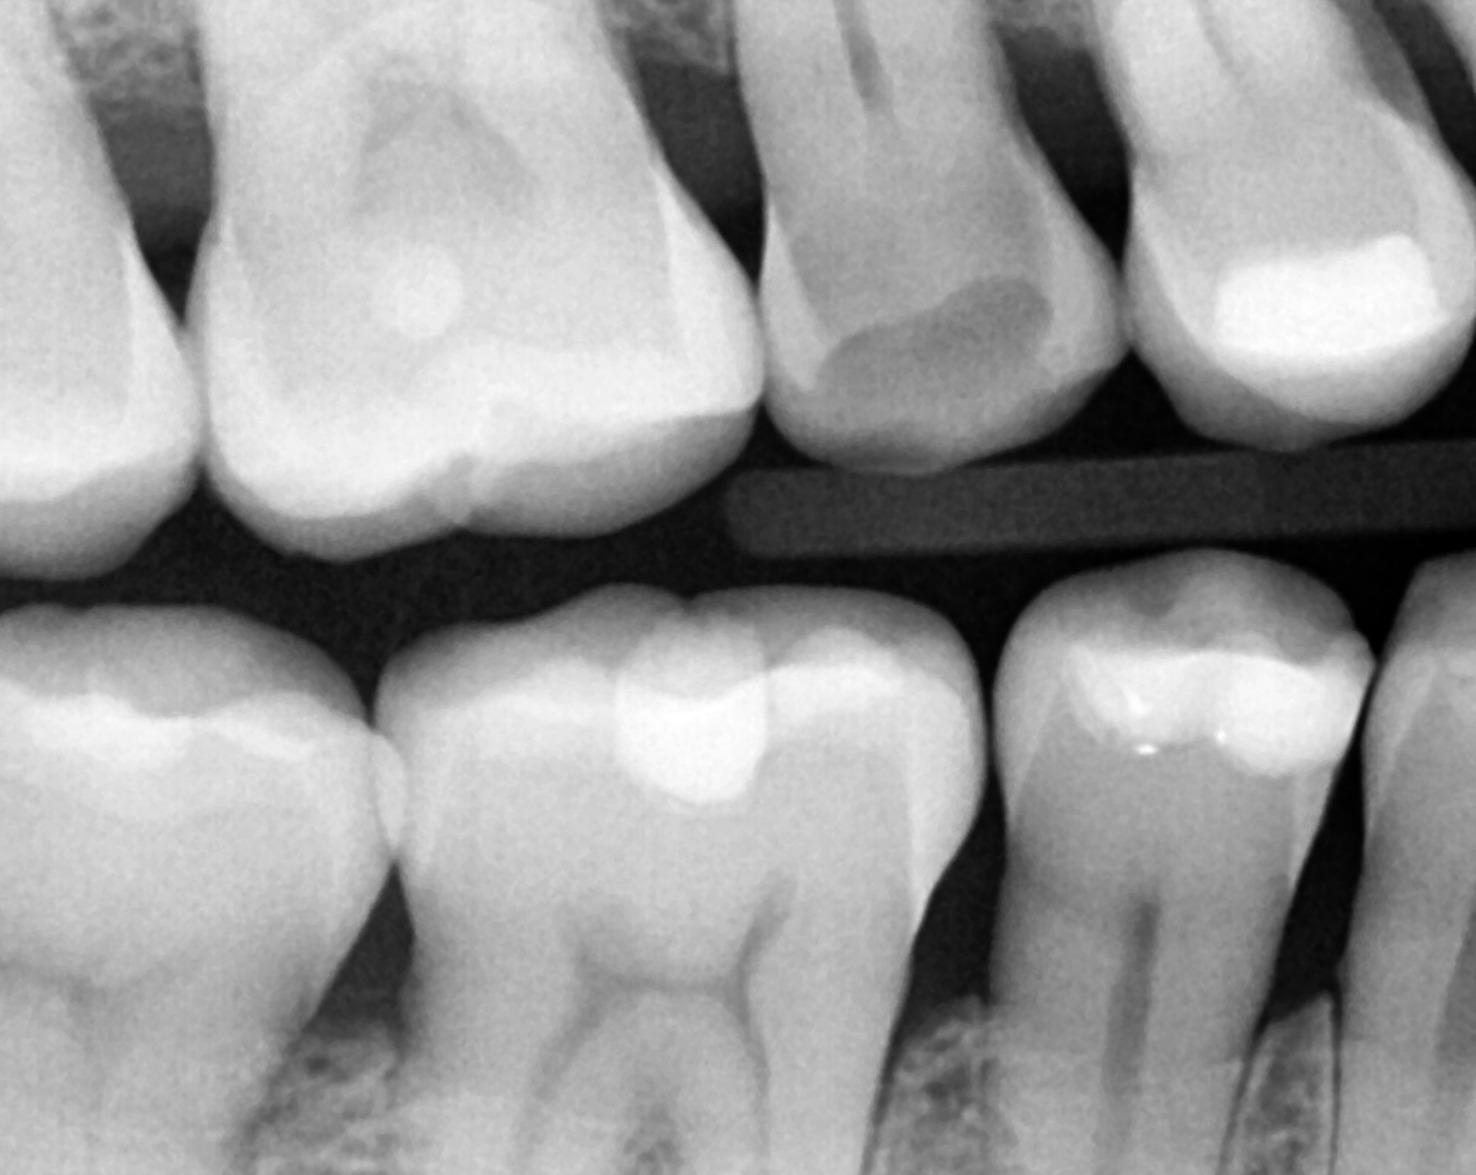

Radiographic findings:

- • No periapical radiolucency

- • Intact PDL

Pre Op PA #4

Bite wing #4 showing fracture line extending to pulp